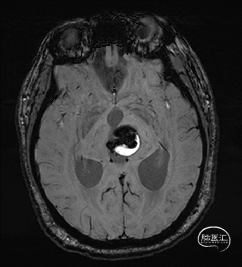

术前MRI检查

术前MRI检查提示左侧丘脑中脑海绵状血管瘤并卒中,梗阻性脑积水;

诊断:1.左侧丘脑中脑海绵状血管瘤并卒中,2.梗阻性脑积水;

年轻患者,较短时间内发生左侧丘脑二次出血,出现右侧面部及上肢麻木,复视,第二次出血后并发梗阻性脑积水,出现头痛。结合病史、神经系统体征、头颅CT及MRI检查,诊断左侧丘脑及中脑CM并卒中、脑积水明确,并导致了神经功能障碍,具备手术指征。

本例患者磁共振检查清晰显示病变位于左侧丘脑中脑区域,且位于丘脑内下方向中脑顶盖延续,病变的上部、前部、外侧部都有重要的神经组织,因此,手术从上方、前方、外侧方向切除病变均难以实施;